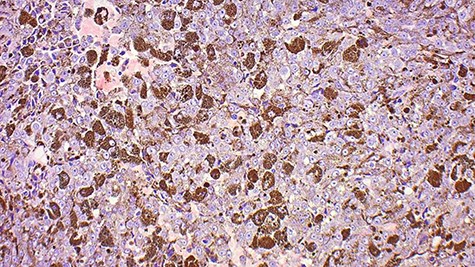

The patient was followed up at the surgical outpatients clinic (Fig. 2). Histology confirmed that the tissue was composed of atypical, heavily pigmented melanocytes and was negative for BRAFV600 mutation (Fig. 3). She was referred for review by an oncologist and a dermatologist. A positron emission tomography–computed tomography (PET–CT) scan showed a sizeable focus of abnormal increased uptake in the right temporalis region with no other evidence of abnormal tracer accumulation. She was later started on nivolumab for Stage 4 melanoma, but within 4 months was noted to have developed local progression of disease and new liver metastasis on a follow-up PET–CT scan. She is currently being managed palliatively.

This image shows a tumour comprised of neoplastic epithelioid cells with prominent central nucleoli, most of which feature cytoplasmic melanin.